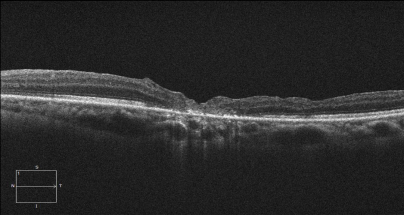

患者陈某,女,48岁,因左眼视物变形半年入院,入院时左眼视力为0.02,诊断为左眼黄斑裂孔,在我科行左眼玻璃体切割联合内界膜填塞术后,患者自觉视物变形症状明显好转,术后一月门诊复查左眼视力提高到0.12,黄斑裂孔已修复。门诊复查左眼黄斑区OCT如下图所示: